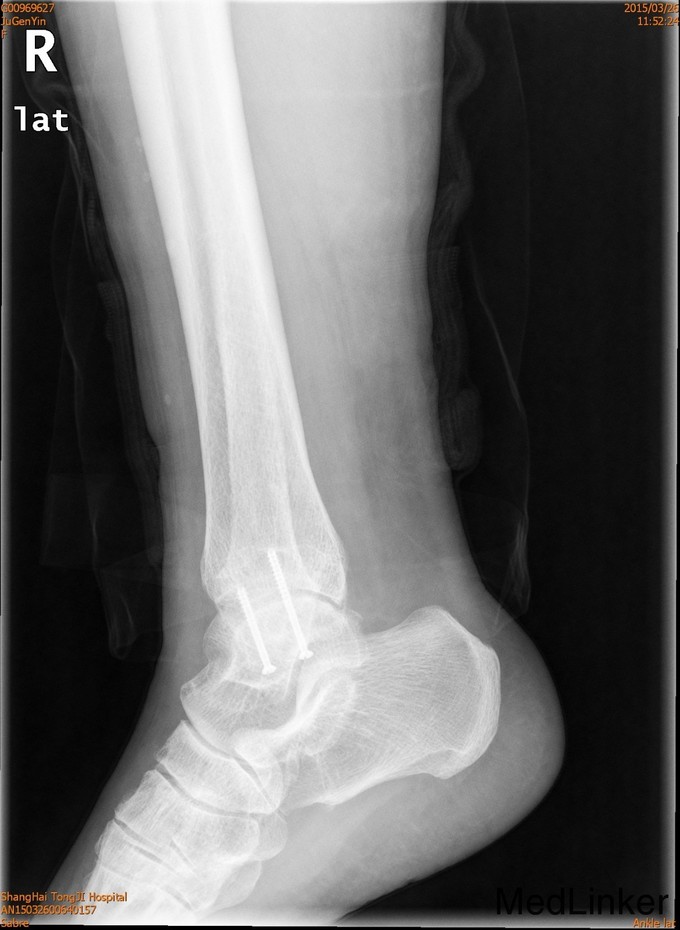

2年后随访患者活动可,内固定位置可,螺钉未予取出。外踝骨折可导致踝关节不稳定,手术治疗效果可。